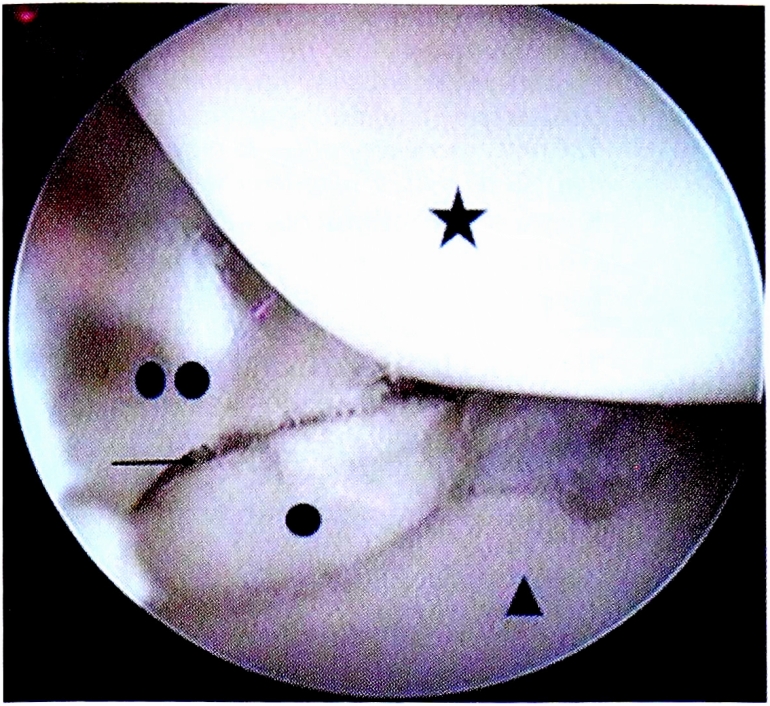

Визуализировали зону ложного сустава (рис. 2).

Рис. 2. Артроскопическая анатомия среднезапястного сустава. Звездочкой обозначена ладьевидная кость (scaphoid); треугольником — полулунная кость (lunate); один круг — проксимальный фрагмент ладьевидной кости (the proximal pole of the scaphoid); два круга — дистальный полюс ладьевидной кости (the distal pole of the scaphoid); стрелка — ложный сустав ладьевидной кости (scaphoid pseudarthrosis).

Fig. 2. Arthroscopic anatomy of the midcarpal joint.